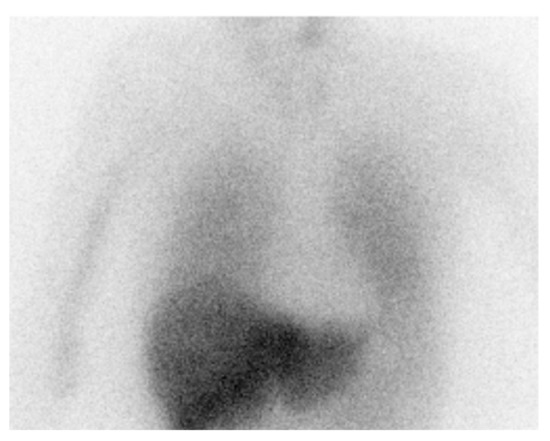

Abnormal cardiac uptake of 123I-metaiodobenzylguanidine (123I-MIBG) is a diagnostic marker of LBD [153]. Prior findings suggest that cardiac sympathetic function in DLB is severely impaired even in the early disease stage, with the uptake of [123I]MIBG being significantly lower than that in patients with PD without dementia [154] (see Figure 4). 123I-MIBG scintigraphy is useful to distinguish PD and DLB from other diseases [155], and to discriminate between DLB and AD [21,156] and other parkinsonian disorders [157]. However, specific data comparing DLB and PDD are not available and 123I-MIBG imaging is unlikely to differentiate PDD from DLB [39,158]. Given its diagnostic accuracy in differentiating DLB from AD, MIBG scintigraphy has been included as an indicative biomarker in the current DLB diagnostic criteria [14]. However, false positive MIBG scintigraphy results due to age, medications, and comorbidities such as diabetes or thyroid dysfunction may limit its use as a routine clinical technique [159].

Figure 4. 123I-MIBG myocardial scintigraphy image taken 3 h after injection. The image shows reduced uptake on 123I-MIBG in the heart, indicative of dysfunction in the postganglionic sympathetic cardiac innervation.